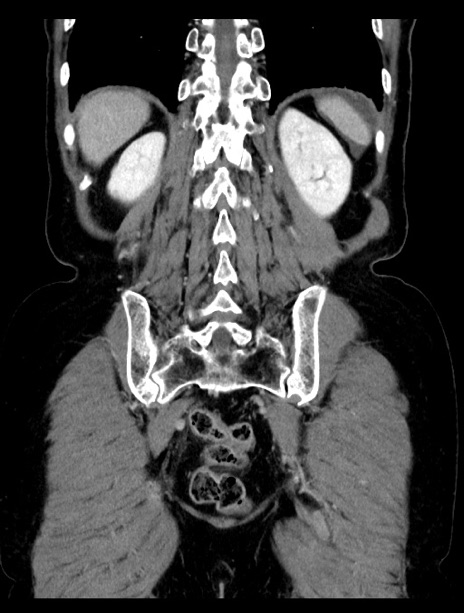

症例23(冠状断像)

【症例】70歳代女性

【主訴】下腹部痛・嘔吐

【現病歴】2日前より腹痛あり。昨日嘔吐あり。症状改善しないため来院。

【既往歴】胃GISTに対して胃部分切除後。

【身体所見】BT 37.1℃、BP 128/77mmHg、腹部:平坦・軟、下腹部に圧痛あり。

【データ】WBC 10200、CRP 0.31